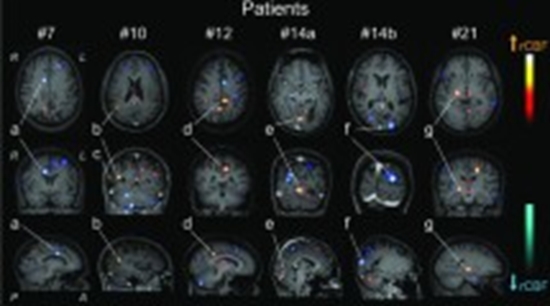

Perfusion weighted MRI patterns in neuropsychiatric systemic lupus erythematosus: a systematic review and meta-analysis

Background: Neuropsychiatric Systemic Lupus Erythematosus (NPSLE) is a complex manifestation of Systemic Lupus Erythematosus (SLE) characterized by a wide range of neurological and psychiatric symptoms. This study aims to elucidate the patterns of Perfusion-Weighted MRI (PWI) in NPSLE patients compared to SLE patients without neuropsychiatric manifestations (non-NPSLE) and healthy controls (HCs).

Material and methods: A systematic search was conducted in PubMed/Medline, Embase, Web of Science, and Scopus for studies utilizing PWI in NPSLE patients published through April 14, 2024. Cerebral blood flow (CBF) data from NPSLE, non-NPSLE patients, and HCs were extracted for meta-analysis, using standardized mean difference (SMD) as an estimate measure. For studies lacking sufficient data for inclusion, CBF, cerebral blood volume (CBV), and mean transit time (MTT) were reviewed qualitatively.

Results: Our review included eight observational studies employing PWI techniques, including dynamic susceptibility contrast (DSC) and arterial spin labeling (ASL). The meta-analysis of NPSLE compared to non-NPSLE incorporated four studies, encompassing 104 NPSLE patients and 90 non-NPSLE patients. The results revealed an SMD of -1.42 (95% CI: -2.85-0.00, I2: 94%) for CBF in NPSLE compared to non-NPSLE.

Conclusion: PWI reveals informative patterns of cerebral perfusion, showing a significant reduction in mean CBF in NPSLE patients compared to non-NPSLE patients. Our qualitative synthesis highlights these changes, particularly in the frontal and temporal lobes. However, the existing data exhibits considerable heterogeneity and limitations.